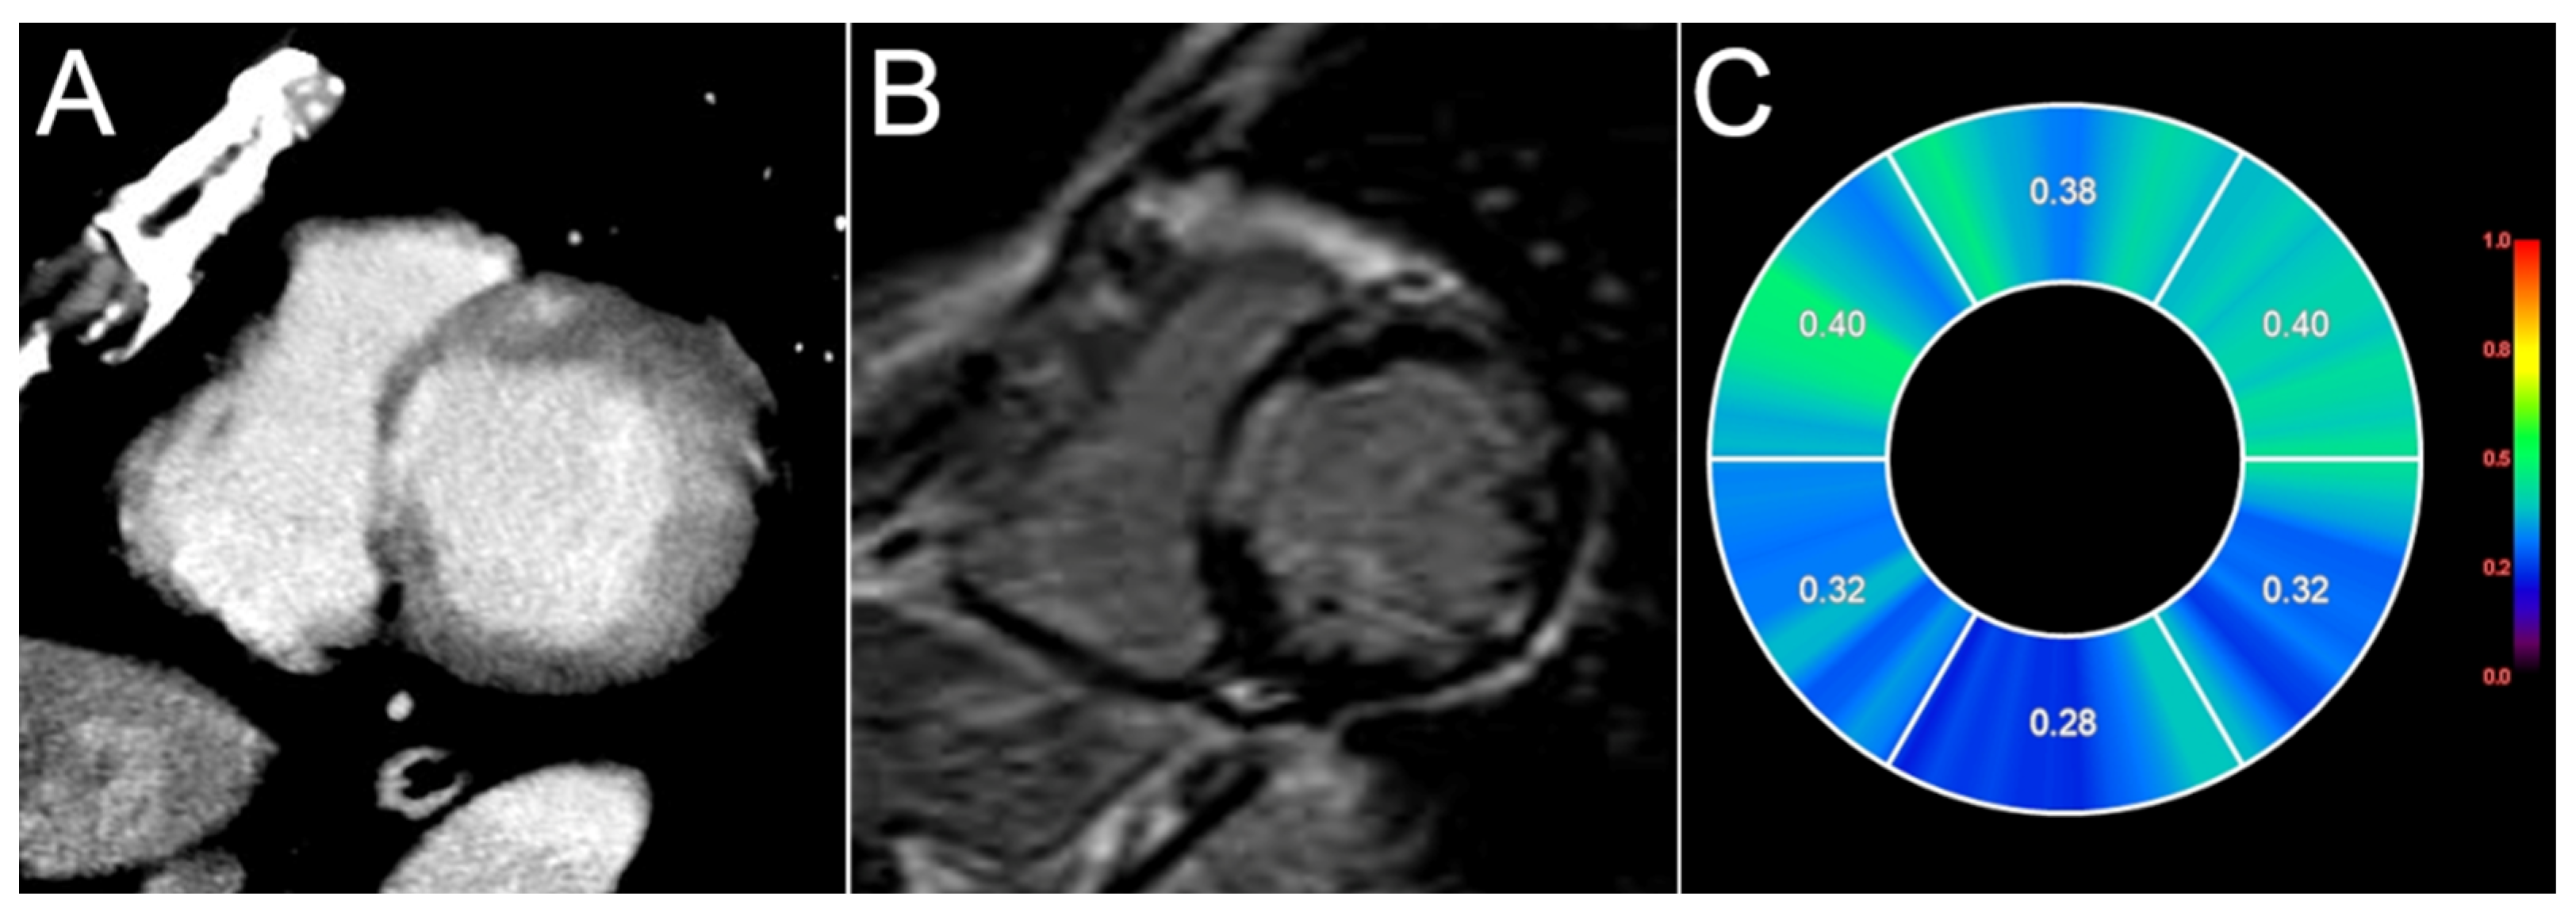

- Aikawa, T.; Oyama-Manabe, N.; Naya, M.; Ohira, H.; Sugimoto, A.; Tsujino, I.; Obara, M.; Manabe, O.; Kudo, K.; Tsutsui, H.; et al. Delayed Contrast-Enhanced Computed Tomography in Patients with Known or Suspected Cardiac Sarcoidosis: A Feasibility Study. Eur. Radiol. 2017, 27, 4054–4063. [Google Scholar] [CrossRef]

- Tsuneta, S.; Oyama-Manabe, N.; Hirata, K.; Harada, T.; Aikawa, T.; Manabe, O.; Ohira, H.; Koyanagawa, K.; Naya, M.; Kudo, K. Texture Analysis of Delayed Contrast-Enhanced Computed Tomography to Diagnose Cardiac Sarcoidosis. Jpn. J. Radiol. 2021, 39, 442–450. [Google Scholar] [CrossRef] [PubMed]